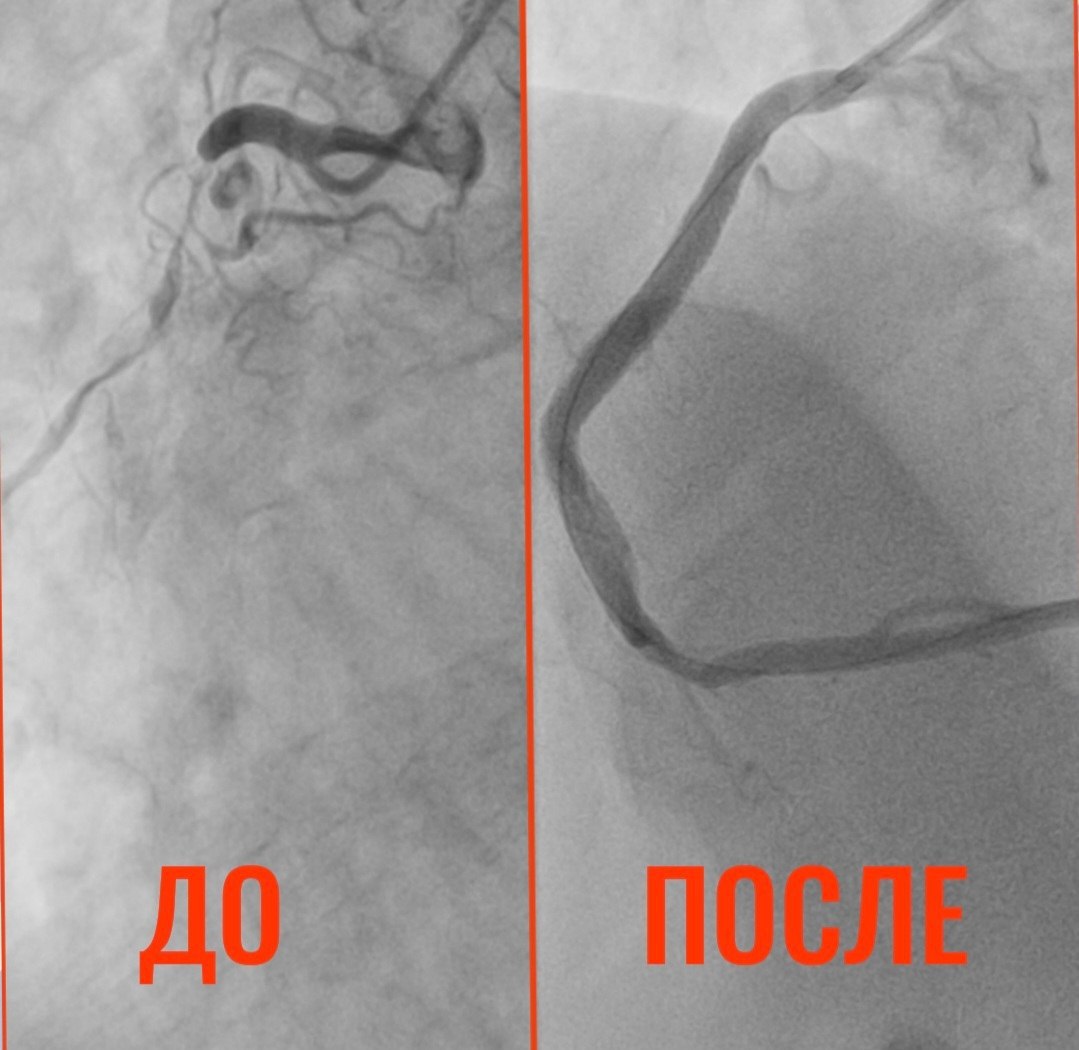

При выполнении коронарографии врачи были шокированы: сужение просвета коронарной артерии достигло 90%. Кровь почти перестала поступать к сердцу.

Состояние сосудов 32-летнего мужчины были сравнимы с изменениями, характерными для глубокой старости, - рассказали в больнице.

Чтобы предотвратить инфаркт, врачи провели пациенту стентирование. Сейчас состояние мужчины стабильно.